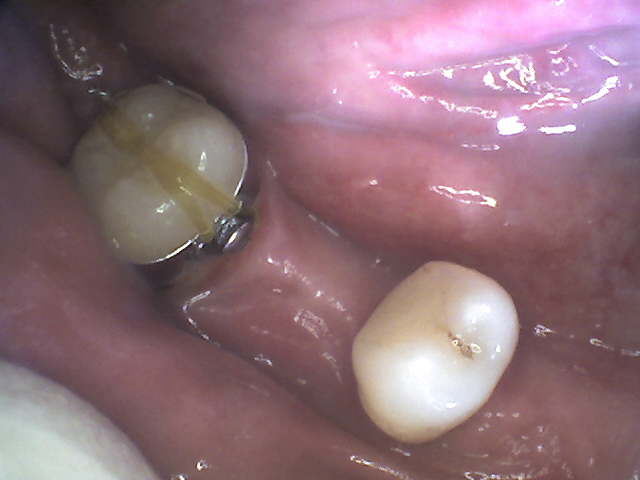

Soggetto di sesso maschile che si è rivolto al nostro studio per la risoluzione di una condizione di edentulia inferiore. Dopo un serie di estrazioni di residui radicolari è stata approntata una protesi provvisoria. Vi era però la necessità di recuperare lo spazio in zona molare 4.6 per l'inserimento di un impianto osteointegrato.

Non era possibile utilizzare una apparecchiatura multi brackets a causa sia della protesi mobile che dell'unico dente in posizione 4.5.

Trattamento: E' stata inserita una minivite ortodontica in posizione 4.8 ed eseguita una trazione diretta in senso distale sul 4.7. Il recupero di spazio ha richiesto 5 mesi.

1 volta al mese abbiamo riattivato la trazione.